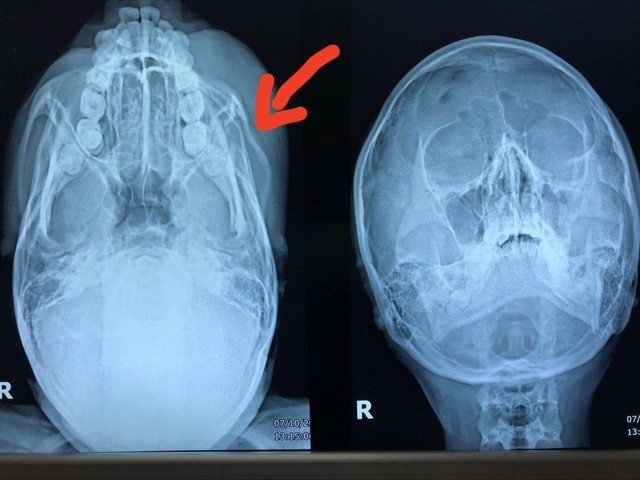

Bệnh nhân được đưa đến Bệnh viện Việt Nam - Cu Ba, cấp cứu ngày 10/7 trong tình trạng mặt mũi xây xát, vùng mắt sưng nề, ảnh hưởng thị lực, gãy gò má.

Bác sĩ Nguyễn Thanh Thái, Trưởng khoa Phẫu thuật Tạo hình hàm mặt, Bệnh viện Việt Nam - Cu Ba, hôm nay cho biết vừa tiến hành phẫu thuật tạo hình nắn chỉnh xương gò má cho bệnh nhân.

"Kíp mổ đã chỉnh lại xương, đặt nẹp để xương lành lại như cũ. Hy vọng cuối tuần bệnh nhân có thể xuất viện và tham dự kỳ thi PTTH vào tuần tới", bác sĩ Thái nói.